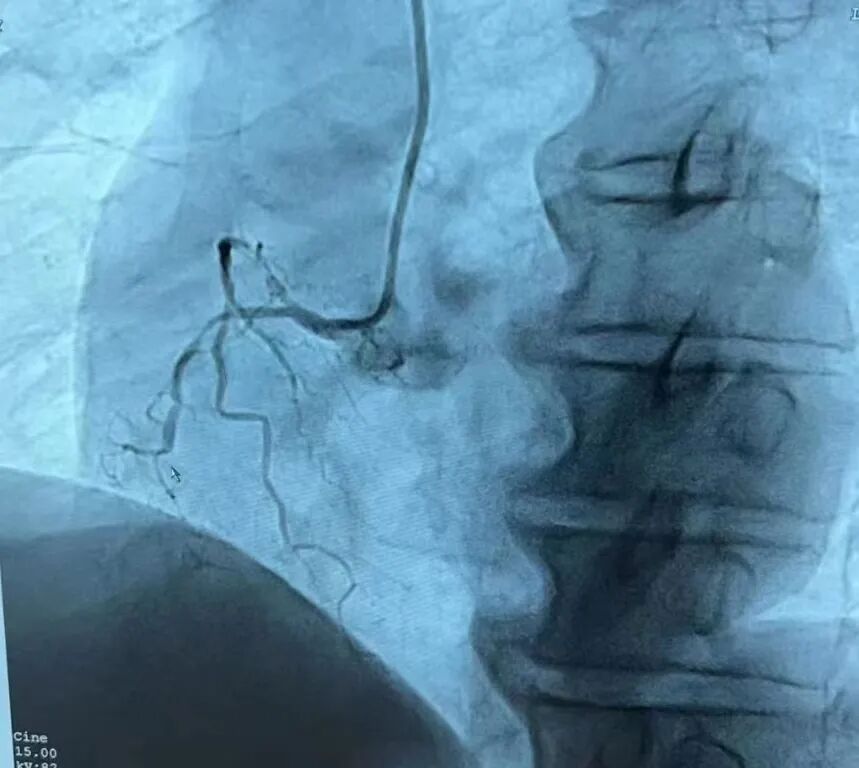

该手术由我院介入医疗团队与中国白求恩介入医学医疗队介入技术帮扶专家合力实施。专家团队快速消毒、铺巾,穿上重达一二十斤重的铅衣,力求速战速决。整个手术从10:20持续到11:50,共耗时1个多小时,术后造影显示患者血管狭窄消失,支架贴壁良好,患者安返病房,患者及家属对我院细致入微的护理精神、快速有效的反应能力、精湛专业的介入技术赞不绝口。